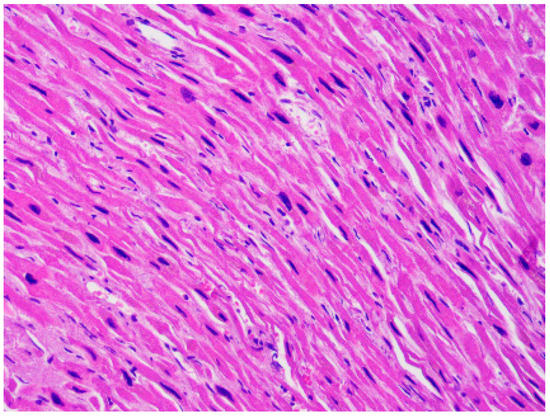

Hypertrophic cardiomyopathy (HCM) has a prevalence of 1/500 [12]. It is macroscopically characterized by abnormal left ventricular (LV) wall thickness and/or heart weight. In HCM the LV hypertrophy is typically asymmetrical, but it can also be symmetrical and can involve only delimited regions, like the apex. The LV wall thickness is considered a strong predictor of sudden death [13]. However, the predisposition to SCD is multifactorial, since it also depends on anamnestic factors (familiarity for SCD and history of syncope and/or non-sustained ventricular tachycardia) [14]. At the autopsy, as said, an abnormal heart weight can be suggestive of HCM, but there is little evidence on what the normal range of this parameter is [15]. However, it is usually assumed that a weight > 500 g is of pathological significance [16]. The diagnostic microscopic features are hypertrophy and disarray (i.e., the loss of the normal parallel alignment of the myocytes), associated with interstitial fibrosis (Figure 1). LV hypertrophy and/or myocardial fibrosis without myocardial disarray are features of uncertain significance [17].

Figure 1. Left ventricle: diffuse disarray and mild fibrosis (A). Hematoxylin and eosin stain, 4× magnification), associated with focal and mild myocardial hypertrophy (B). Hematoxylin and eosin stain, 40× magnification) in a 48-year-old man who suddenly died while playing sport.